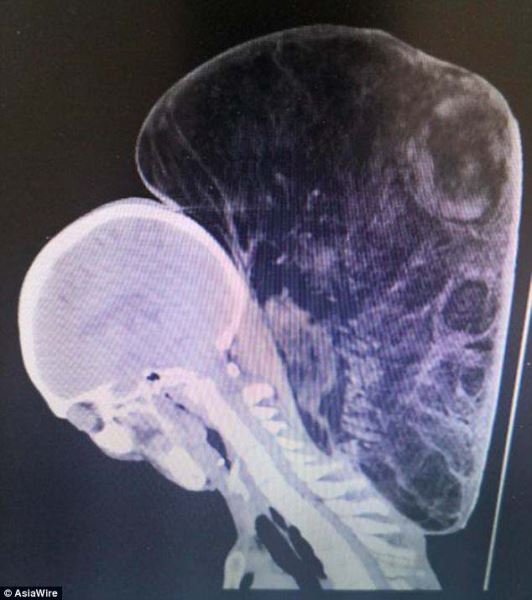

К тому времени опухоль на шее уже стала в несколько раз больше головы и весила 15 кг. Она была такой громоздкой, что уже мешала мужчине сохранять равновесие при ходьбе.

На то, чтобы удалить огромную опухоль с шеи, хирургам клиники провинции Гуйчжоу потребовалось 10 часов. Опухоль оказалась не злокачественной липомой. Такие опухоли вызваны усиленным разрастанием жировых клеток. Чаще всего липомы небольшого размера и лишь при очень запущенном состоянии, как в данном случае, становятся реально огромными.